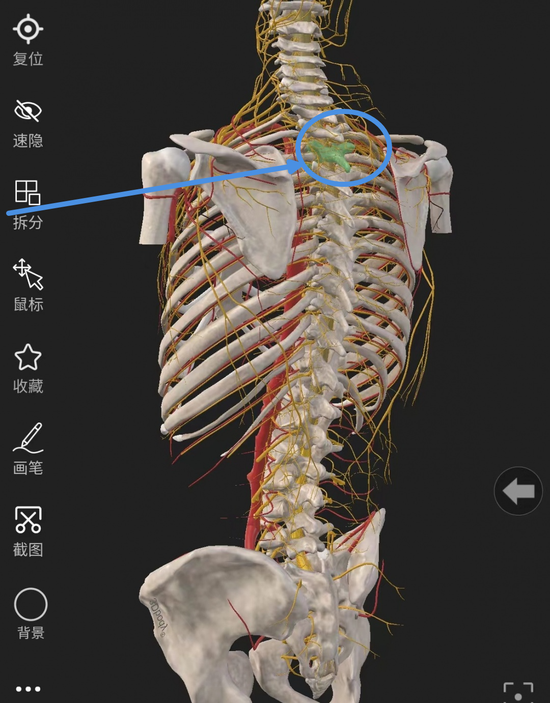

第 三 胸 椎(T 3 椎 体)示 意 图

本次手术的难度主要集中于:空间小(胸椎T3椎体骨折脊柱破坏平面高,手术操作空间极小);距离近(切近于升主动脉弓及脊神经、肺叶);状态差(患者已过期颐之年,又处于食道癌晚期);定位难(双侧肩胛骨与第三胸椎平齐,透视难度大)。手术的难度远远超出了一般骨科手术的范围,甚至有些困难,在医院都没有前例可循。如何翻越压在病患身上的“四座大山”,成为了医护人员深思苦索的头等大事。